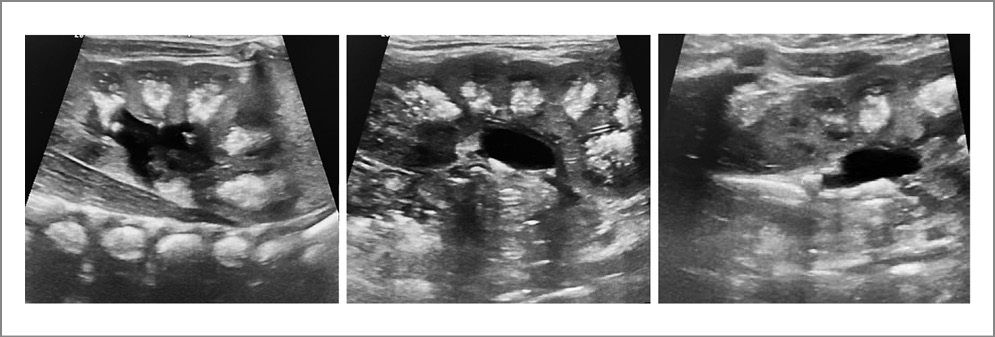

У большинства недоношенных детей СГП выявлен к концу 1-го месяца жизни – 25±6 дней. В группе I у 74% детей данные изменения носили двусторонний характер, а у 26% отмечены с одной стороны. При этом у 15 (2%) детей уже на II этапе выхаживания выявлены гиперэхогенные включения, дающие акустические тени и симптом «мерцающего артефакта» в режиме цветового допплеровского картирования, которые интерпретированы как конкременты почек. Эти дети продолжали амбулаторное наблюдение в постнеонатальном периоде (рис. 1).

Рис. 1. Ребенок в возрасте 6 мес. Родился со сроком гестации 28 нед, массой тела 790 г. На эхограммах почек – СГП, у входа в мочеточник определяется конкремент